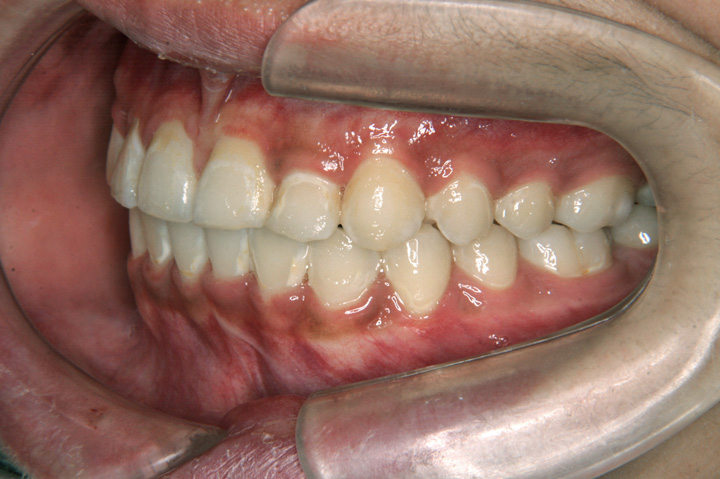

下顎前突(受け口)

叢生(乱ぐい歯)

臼歯部不正(交叉咬合など)

受け口を主訴に来院された7歳11ヶ月の患者さんです。前歯部反対咬合は機能性の要因もあったため、リンガルアーチとチンキャップを併用し、前歯部のかみ合わせを改善することを優先しました。その後、非抜歯でエッジワイズ装置を用いて配列を行いました。